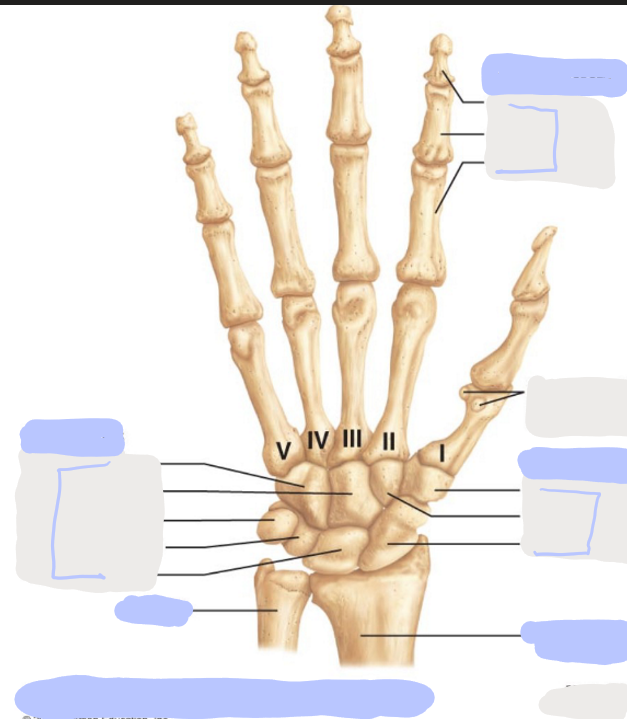

What is this picture of?

Posterior View of the Right Hand

What is here?

Where is the Ulna?

What is here?

Where is the Radius?

What is here?

Where are the Metacarpals?

What is here?

Where are some of the Carpals?

What is here?

Where are some of the Carpals?

How many carpals are there?

8

How many metacarpals are there?

5

How many phalanges are there?

14